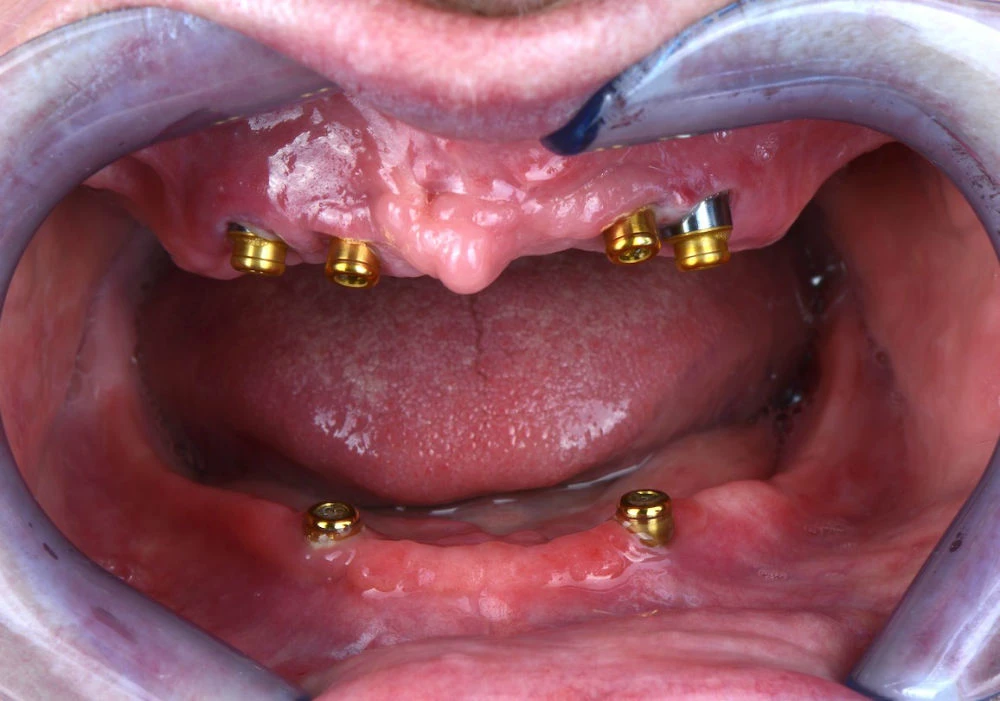

Възможно е да се ползват две различни задържащи системи върху зъбните импланти.

- О-Ball система – тя е по-старо поколение.

2. Locator система – тя е по-ново поколение.

/горна челюст – 4 зъбни импланта/

/долна челюст – 2 зъбни импланта/